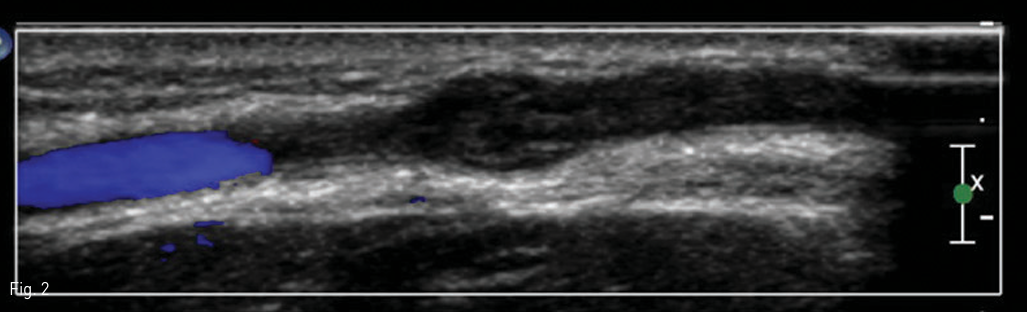

오른쪽 전완부 초음파 검사에서 환자가 압통 및 발적을 호소한 부위에는 피하부종이 보였다. 색 도플러 검사에서는 이 부위에 늘어난 팔 오금 중간 정맥 (median cubital vein) 이 보였고, 정맥 내에 긴 분절 형태의 고 에코 혈전이 있었다 (Fig. 1). 늘어난 팔 오금 중간 정맥에 정맥 혈류는 전혀 보이지 않았다 (Fig. 2). 그 외의 자쪽 피부 정맥 (basilic vein), 노쪽 피부 정맥 (cephalic vein), 그리고 심부 정맥 (deep vein)들 내에는 혈전은 보이지 않았고, 정상 혈류가 유지되고 있었다.

Fig 2

Color Doppler ultrasound does not depict blood flow in the thrombosed right median cubital vein.